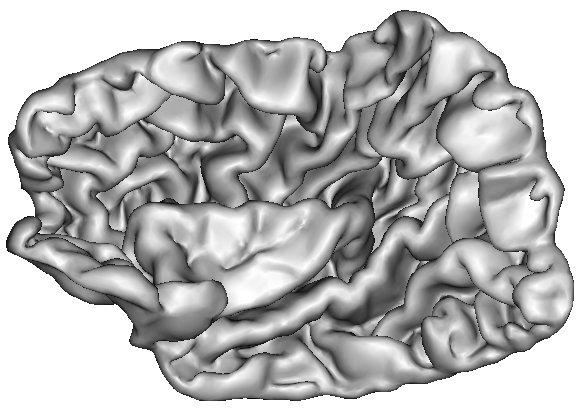

The resulting grey/white interface can be converted into a mesh endowed with the spherical topology, which will be inflated by some other Brainvisa treatments for visualization purpose (Ana Inflate Cortical Surface):

A dilation of this interface towards the outer brain edges may lead to nice 3D rendering of the cortical surface, which are easy to read because the folds are opened (Ana Get Opened Hemi Surface) :